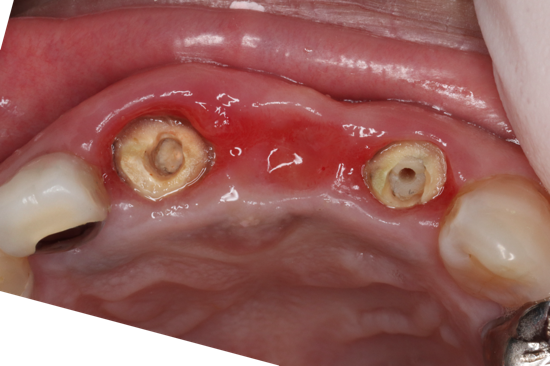

抜歯即時インプラント症例写真

抜歯と同時にインプラント埋入から仮り歯まで入れるので、手術回数が少なく、歯のない期間がないことが最大のメリットとなります。

同日にインプラント埋入から仮り歯まで作成した。

その後歯肉の形態を揃えるために歯肉移植を行い、3ヶ月治癒を待った

その後最終の型取りをスキャンし、完成した

治療期間:約6ヶ月